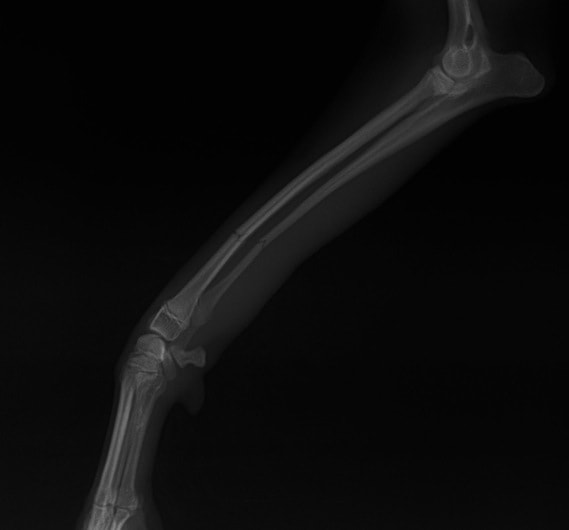

ペルシャ猫 11ヶ月齢 雄

他院にて左大腿骨遠位の成長板骨折(salter-harrisⅠ型)が認められており、治療相談を目的として来院。当院にて、キルシュナーワイヤーを用いたピンニングにより骨折部位の整復を行いました。術後の経過は良好で、現在も経過観察中です。

術後レントゲン